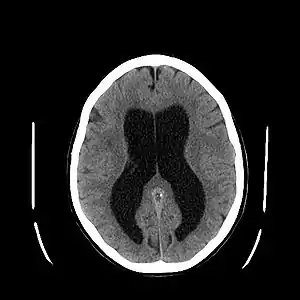

| سیتی اسکن از مغز دچار هیدروسفالی. | |